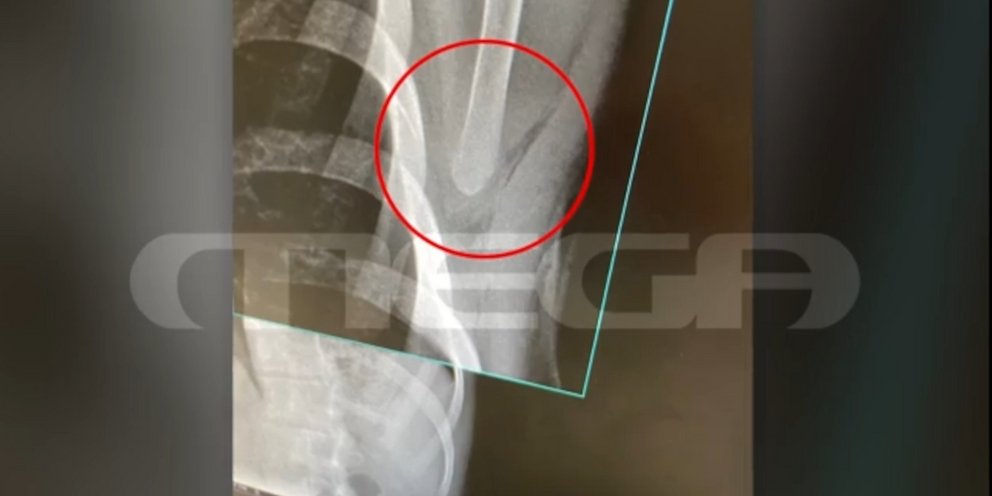

Οι δράστες στη συνέχεια έβγαλαν τα κατσαβίδια και ένας εξ αυτών κάρφωσε τον νεαρό στην πλάτη. Το τραύμα του ήταν βαθύ, όπως αποτυπώνεται και στην ακτινογραφία του θύματος της επίθεσης, και απείλησε ζωτικά του όργανα.